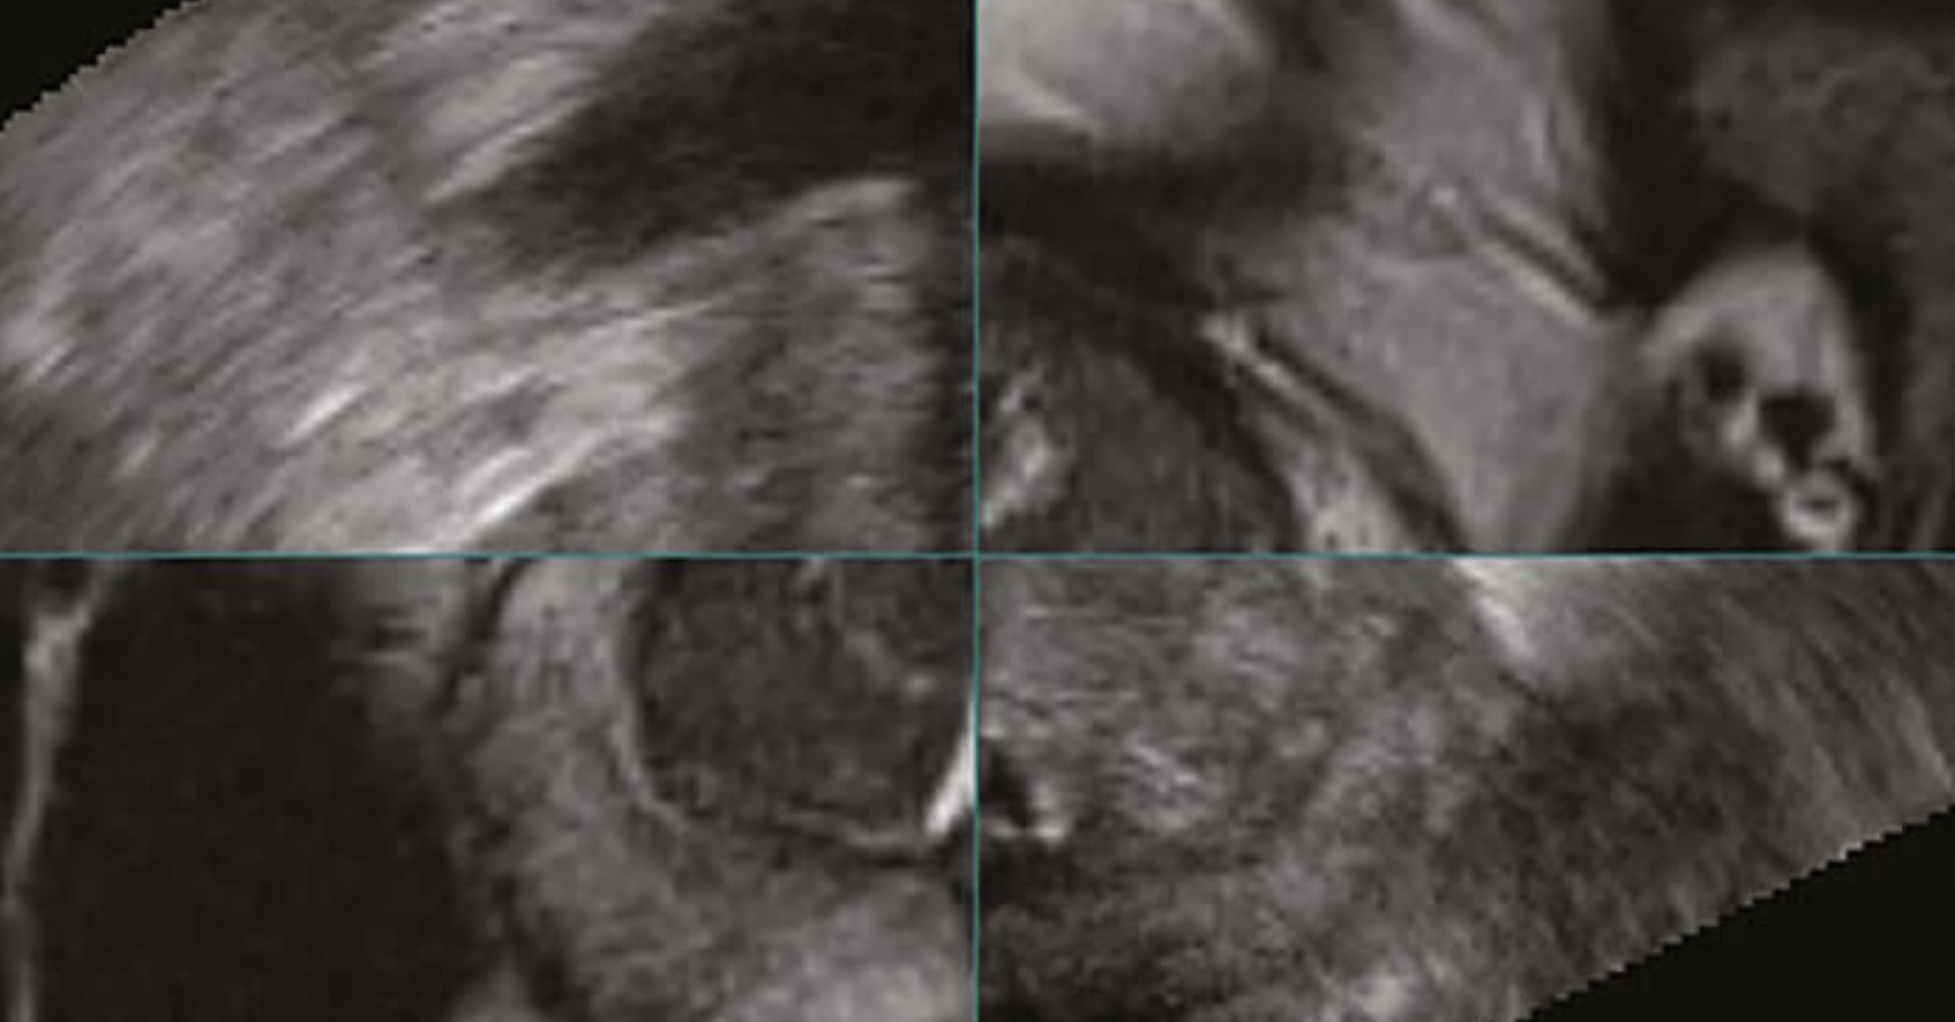

Biopsia de Fusion con sistema KOELIS

La biopsia prostática por fusión es una tecnología exitosa que se hace posible superponiendo imágenes de la próstata con secuencias de resonancia magnética para visualizar y localizar las lesiones. Las zonas sospechosas detectadas por la resonancia magnética se muestran de este modo en el escáner de ultrasonido (ecógrafo), permitiendo que el médico Urólogo realice las biopsias necesarias en tiempo real. La transparencia precisa (fusión) de las imágenes de resonancia magnética-ultrasonido es el primer paso esencial para obtener un mayor nivel de precisión durante el procedimiento.